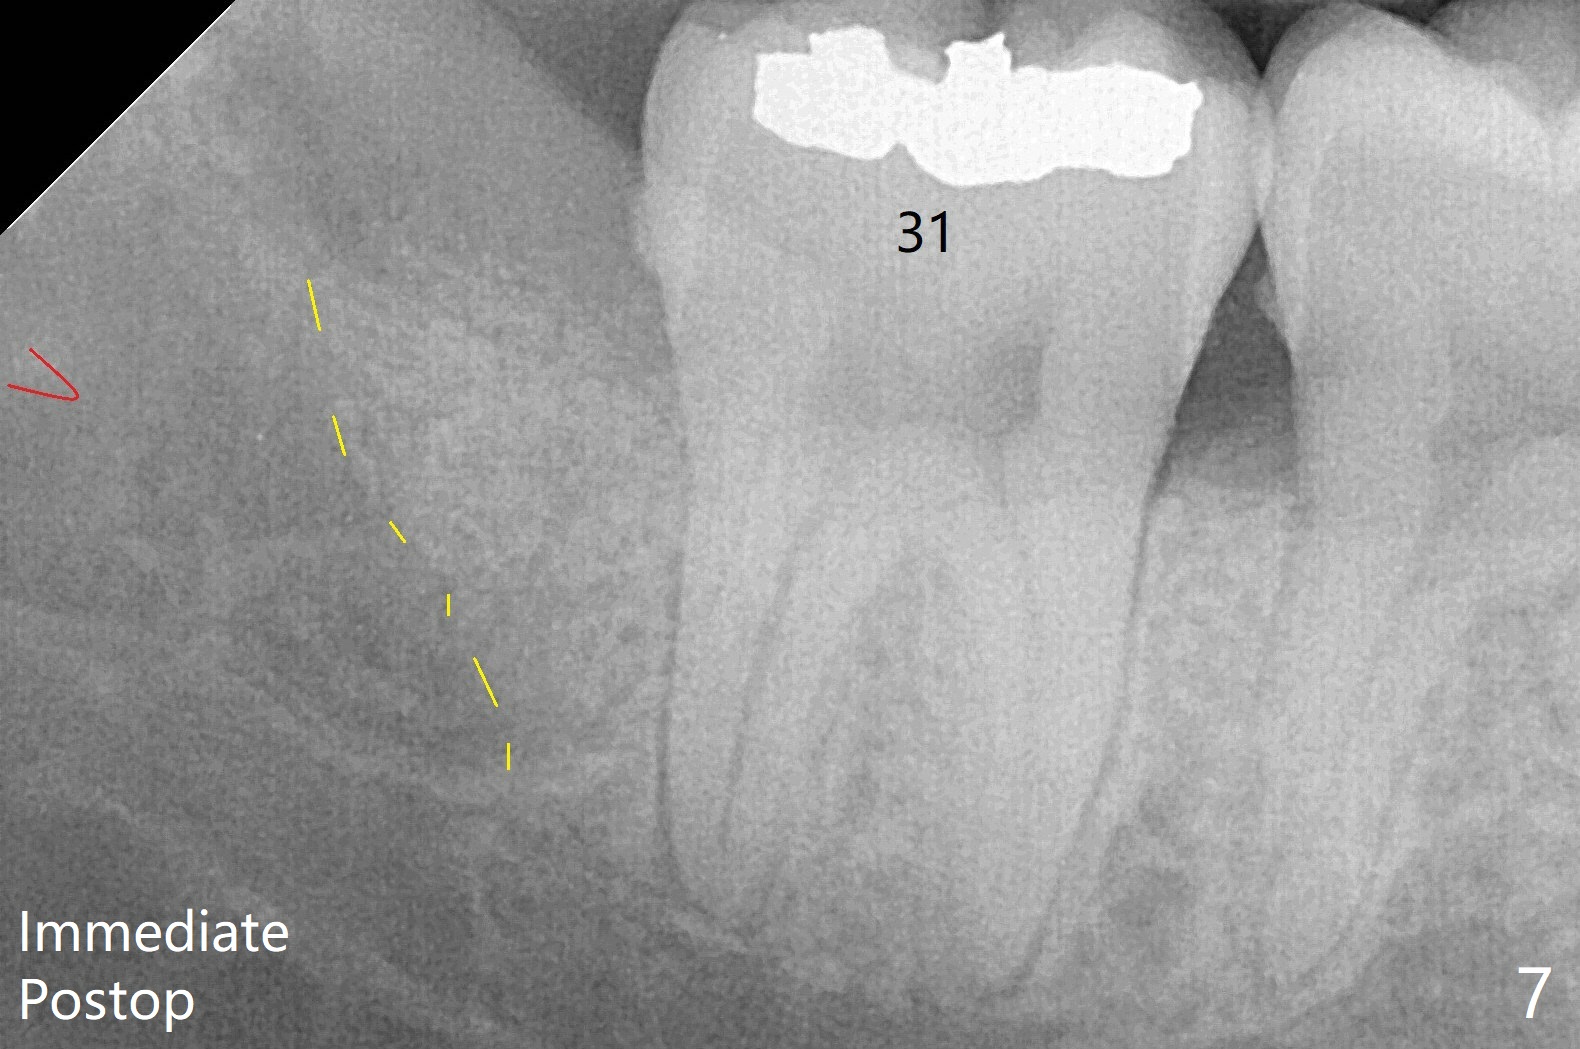

The bone fills the whole socket 1 year postop (Fig.8); there is no root surface exposure at #31.